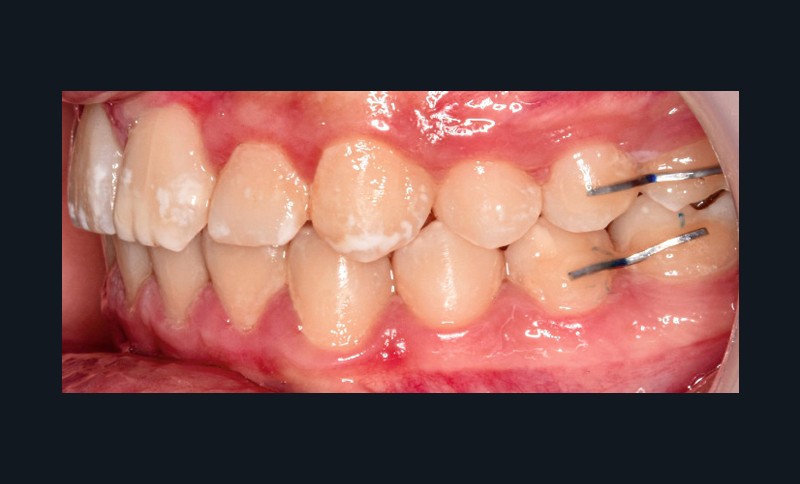

Sur le plan alvéolo-dentaire (fig. 1b) :

- Classe II subdivision gauche avec déviation du point inter-incisif mandibulaire à gauche ;

- occlusion inversée entre 22 et 32 ;

- dysharmonie dento-arcade (DDA) sévère ;

- 13 en position haute retenue.